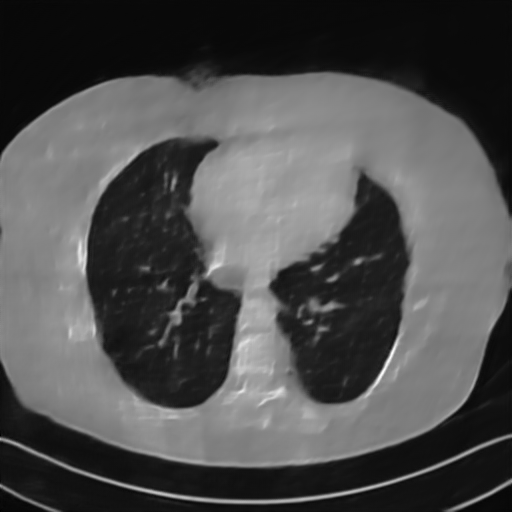

Fig. 4 presents the reconstruction results and residual images obtained by different methods for limited-angle reconstruction. As can be seen, the learning-based methods outperform the direct method and TV model, which exhibit serious artifacts in the missing angle region. Although the denoiser introduced by the FBP-Unet can somehow deal with the noises, the result still presents obvious artifacts. Compared to the SIPID, PD-net and FSR-nets, our LRIP-net1/2 can better preserve the image details and edges with less information left in the residual images. Thus, both the quantitative and qualitative results confirm that the low-to-high double-resolution strategy can improve the reconstruction accuracy for the limited-angle reconstruction problem.

We observe that the low-resolution image prior plays an important role in our method. More specifically, we compare the results of our LRIP-net with respect to different low-resolution priors, which are obtained by down-sampling rate of 1/2, 1/4, and 1/8, respectively. As can be seen in Table III, the best reconstruction results are obtained with the image prior reconstructed by the down-sampling rate of for 150∘, 120∘ and 90∘ limited-angle reconstruction. The visual comparison based on different image priors are also provided in Fig. 5, where obviously less artifacts are left in the reconstruction image by LRIP-net1/8. By comparing the running time, it is easy to see that the smaller the low-resolution image prior, the faster the LRIP-net works.

We further increase the noise level contained in the raw data to 10% white Gaussian noises and list the quantitative results in Table IV. It can be observed that the reconstruction performance of the TV model is poor in the case of high-level noises with PSNR dropping by 4 to 5 dB compared to the previous experiments. On the other hand, the performance of the learning-based methods is less sensitive to noises. The SIPID method relying on the sinogram interpolation works better than FBP-Unet. And the deep unrolling methods (i.e., PD-net, IFSR-net, SFSR-net) outperform the traditional iterative algorithm when the scanning range is limited and data is corrupted by noises. Similar to the previous experiments, compared with other deep learning algorithms, our LRIP-nets give the reconstruction results with higher PSNR and SSIM. Moreover, the low-resolution image obtained by the projection data down-sampled with rate 1/8 always gives the best reconstruction results with more than 2 dB PSNR and 0.05 SSIM increments compared to the PD-net. Fig. 6 illustrates the reconstructed images from different methodologies with scanning angular range of and 10% Gaussian noises. It can be seen that the both TV model and the FBP-Unet suffers from significant artifacts, which present distortions in the angular range of the missing scan. Other learning-based methods provides better visual qualities than FBP-Unet, and our LRIP-net1/8 still gives the best reconstruction result with correct boundaries and fine structures.